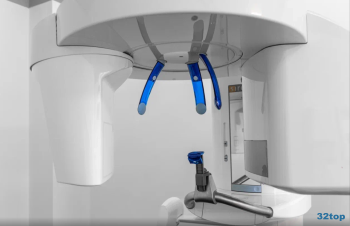

3D-сканер

Компьютерная томографияКомпьютерная томография в Москвеот 2 500 ₽

Панорамный снимок челюстиПанорамный снимок челюсти в Москвеот 1 600 ₽

Рентген зубовРентген зубов в Москвеот 350 ₽